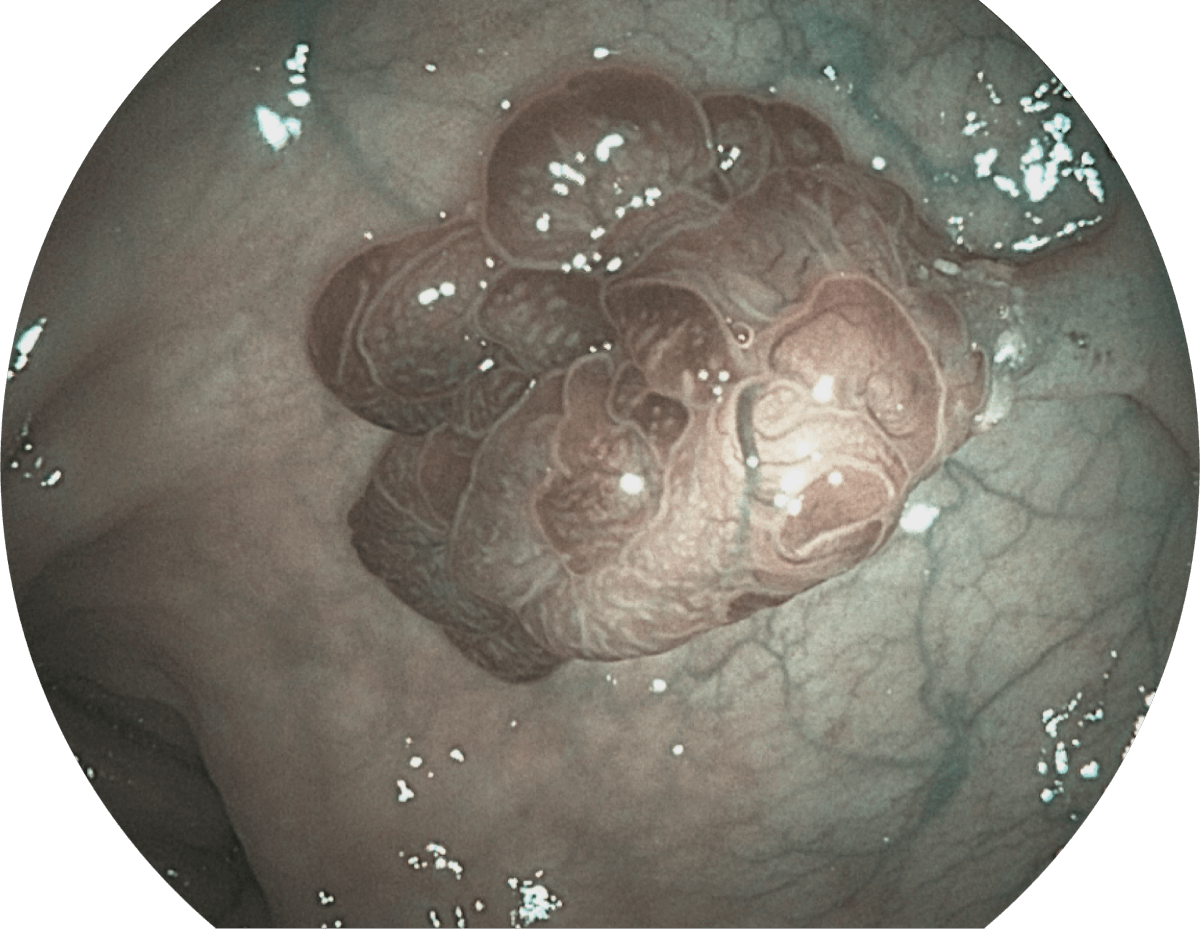

具有聚谱成像技术(SFI)及光电复合染色成像技术(VIST),可完美呈现粘膜细节及病变特征。

WL

SFI

VIST